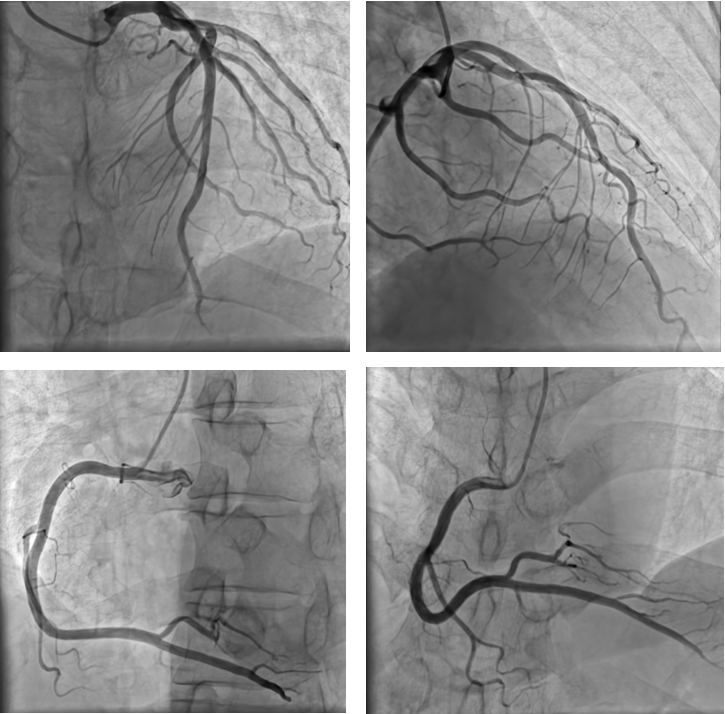

此次全新升级的“零噪声”DSA设备,凭借软硬件同时的系统优化升级,搭载国产自研高压发生器与智能滤过系统,利用多帧融合降噪原理,实现了图像质量的飞跃式提升,它几乎完全消除了图像中的干扰性噪点,图像空间分辨率提升57%,信噪比提升超过4倍。这意味着医生能够像拥有“超级显微镜”一样,更清晰地观察到血管内的微小结构和病变情况。以冠脉造影为例,以往难以察觉的间隔支、对角支等侧支小血管,以及0级和1级侧支循环,如今都能清晰显像。在心血管介入手术中,医生可以更精准地定位病变部位,制定出更科学合理的治疗方案,大大提高了手术成功率。

冠脉影像,脉络分明

在冠脉造影手术中,“零噪声”DSA通过硬件技术与深度学习算法协同创新,将空间分辨率从传统DSA的0.2mm级提升至0.1mm级,实现了对冠状动脉微小分支的超高清显影。

“零噪声”DSA“还原真实血管影像”